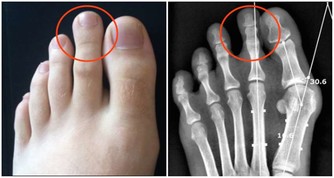

6.骨骼

腿腳靈活運動能力強得5分,偶爾覺得頸椎或腰椎酸痛得3分,很少運動或從來不運動得0分

健康的男性他的骨骼也會很健康,充滿精氣神,熱愛運動,每天再累都會出去健身,所以他們的腿腳很少出現骨骼疾病。而有的人運動頻率少,還長期坐著辦公,時間長了脖子和腰背就會酸痛,關節也容易僵硬。